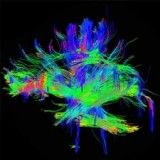

Se quer saber como sair da depressão no Itaim Bibi, entre em contato com a OHR Psiquiatria, onde você terá boas chances de total recuperação da depressão. Disponibilizamos uma série de tratamentos que podem ser usados de forma combinada. A saber: medicamentos convencionais, psicoterapia e infusões de doses baixas de cetamina.